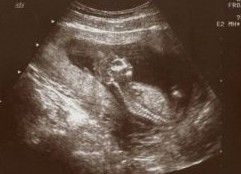

1.超聲檢查:羊水平段>7cm示合併羊水過多,測不出胎兒雙頂徑。B型超音波聲像圖不見胎頭之光環。